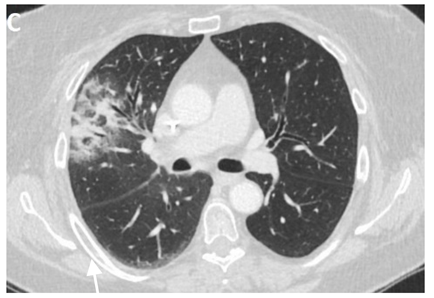

Even though X-ray is non-specific to pneumonitis, it is usually the first investigation performed. During the early phases, the most common finding on chest radiograph is perivascular haziness which frequently progresses to alveolar opacities [39]. Chest radiographs can show ground-glass opacity and/or consolidation in the radiation port. Consolidation usually has a nodular appearance but can be more confluent/lobar along with the irradiated port. Findings can be seen outside the radiation port as well. Some uncommon findings are ipsilateral pleural effusion with or without adjacent atelectasis [66]. Chest radiograph can also show bilateral interstitial infiltrates mimicking heart failure or acute respiratory distress syndrome (ARDS) [69,70]. All irradiated patients usually have some degree of abnormalities in the X-rays. Some fail to show any radiographic evidence of lung injury with pneumonitis. Early features exhibiting mild opacification of vascular markings are common, with later stages showing dense opacities. A radiographic straight-line effect may indicate the direction of the radiation port along the lines of pneumonitis [39,71] (Figure 1).

Figure 1.

Chest X-ray showing radiation pneumonitis Image 1—Frontal chest X-ray showing left upper lobe mass (arrow), the patient also had a right internal jugular port placed. Image 2—Post radiation treatment frontal chest X-ray showing increasing alveolar and interstitial opacities in the left upper lobe and in the left lower lobe in a patient suspected of radiation pneumonitis.

In the event of worsening symptoms after empirical antibiotics, Chest CT may provide more insights. Interestingly, the opacification lines in both X-ray and CT conform to radiation port rather than anatomical lines of lung structure, which could be diagnostic. Identified progression outside the lung field might suggest immune-mediated lymphocytic alveolitis [72]. Various stages of presentation provide different imaging outlooks (Table 3).

During the acute exudative stage, features of ground-glass attenuation or homogeneous consolidation may be noticed. A patchy consolidation that confirms the irradiation portal is also suggestive of the early phase. A discrete consolidation that conforms to the shape of the irradiation portal is proliferative changes of irradiation [71].

A chronic fibrosis stage with features of parenchymal distortion, traction bronchiectasis, and pleural thickening resulting in volume loss and irreversible changes are noticed. Refer to Table 2.